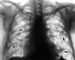

В большинстве случаев больные жалоб не предъявляют, а инфильтраты в легких выявляются случайно при рентгенологическом обследовании. Реже наблюдаются небольшая слабость, покашливание, повышение температуры тела до субфебрильной. Иногда отмечаются легкие астмоподобные проявления. Может выделяться небольшое количество мокроты. При физикальном исследовании грудной клетки часто не удается установить отклонений от нормы, в некоторых случаях можно выслушать в одном или нескольких участках влажные мелкопузырчатые хрипы. В крови отмечается умеренный лейкоцитоз с высокой эозинофилией (до 70%), которая, как правило, достигает своего максимума после появления инфильтратов в легких. Рентгенологически в легких выявляются единичные или множественные относительно больших размеров нечеткие инфильтраты (рис. 1), которые локализуются чаще в верхних отделах субплеврально. По-видимому, это расположение инфильтратов объясняется максимальной концентрацией тучных клеток в субплевральных участках легких. Типичен также «летучий» характер инфильтратов — они могут исчезать через несколько дней (максимальная длительность существования инфильтрата 4 нед.). Если он сохраняется дольше и не имеет тенденции к исчезновению, то диагноз ставится под сомнение и диагностический поиск следует продолжить.